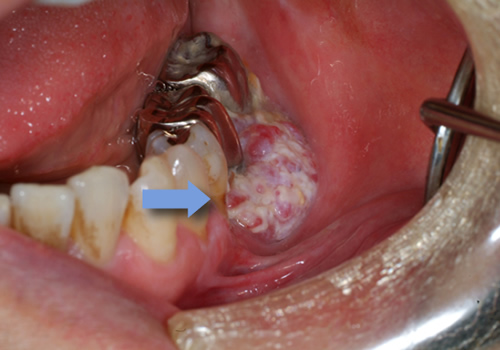

歯肉がん

歯肉に出来る悪性腫瘍は、下顎が多く、有歯顎(歯のある方)臼歯部(奥歯)によく発生します。疫学的には男性が多いです。

無歯顎(歯が全くない方)の患者さんも多いです。口腔に発生するがんの20%弱程度は歯肉がんです。